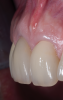

Fig 9. Facial view of clinical appearance of facial tissues at 1-year postoperative follow-up.

Figure 9

Fig 10. Oblique view of single-tooth implant No. 8 (1:1) treated with PET. Note the excellent retention of soft-tissue form around the restoration reflecting maintenance of the supporting buccal plate of bone.

Figure 10